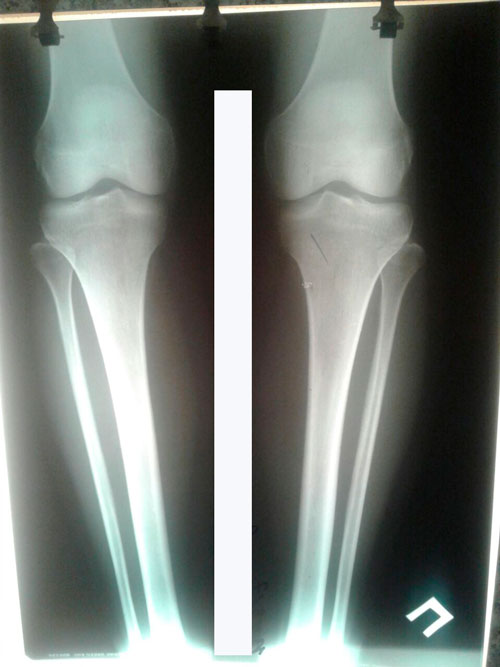

Дата операции 14.03.2017г.

Исходник - 39 лет.

Ротация (двухсторонняя)

РЕНТГЕН ДО ОПЕРАЦИИ